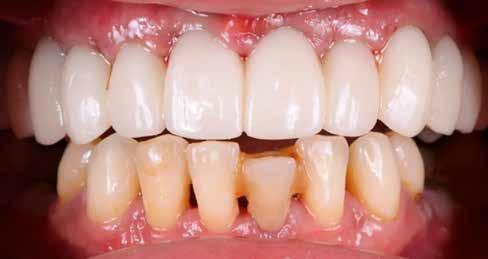

A végleges protetikai ellátást három hónappal az implantációt követően kezdtük meg. Az implantátumok gyógyulása panasz- és tünetmentes volt. Hagyományos, zárt kanalas A-szilikon lenyomatot vettünk (8. a–c ábrák). Egy esetben a gingivális emergenciát sikerült nagy pontossággal lemintázni fényre kötő folyékony kompozit segítségével (Master Flow, Biodinamica; 9. a–c ábrák). Három lítium-diszilikát és egy monolitikus cirkonkorona készült (10. a–b. ábrák), amelyek cementtel rögzültek a végleges protetikai fejeken (Dual RelyX™ U200, 3M; 11. a–b ábrák).

10. a ábra: Végleges lítium-diszilikát koronák. – 10. b ábra: Végleges monolitikus cirkónium-dioxid korona. – 11. a–b ábrák: Klinikai megjelenés tizenkét hónap elteltével. 12. a–b ábrák: Tizenkét hónapos kontrollröntgen-felvételek.